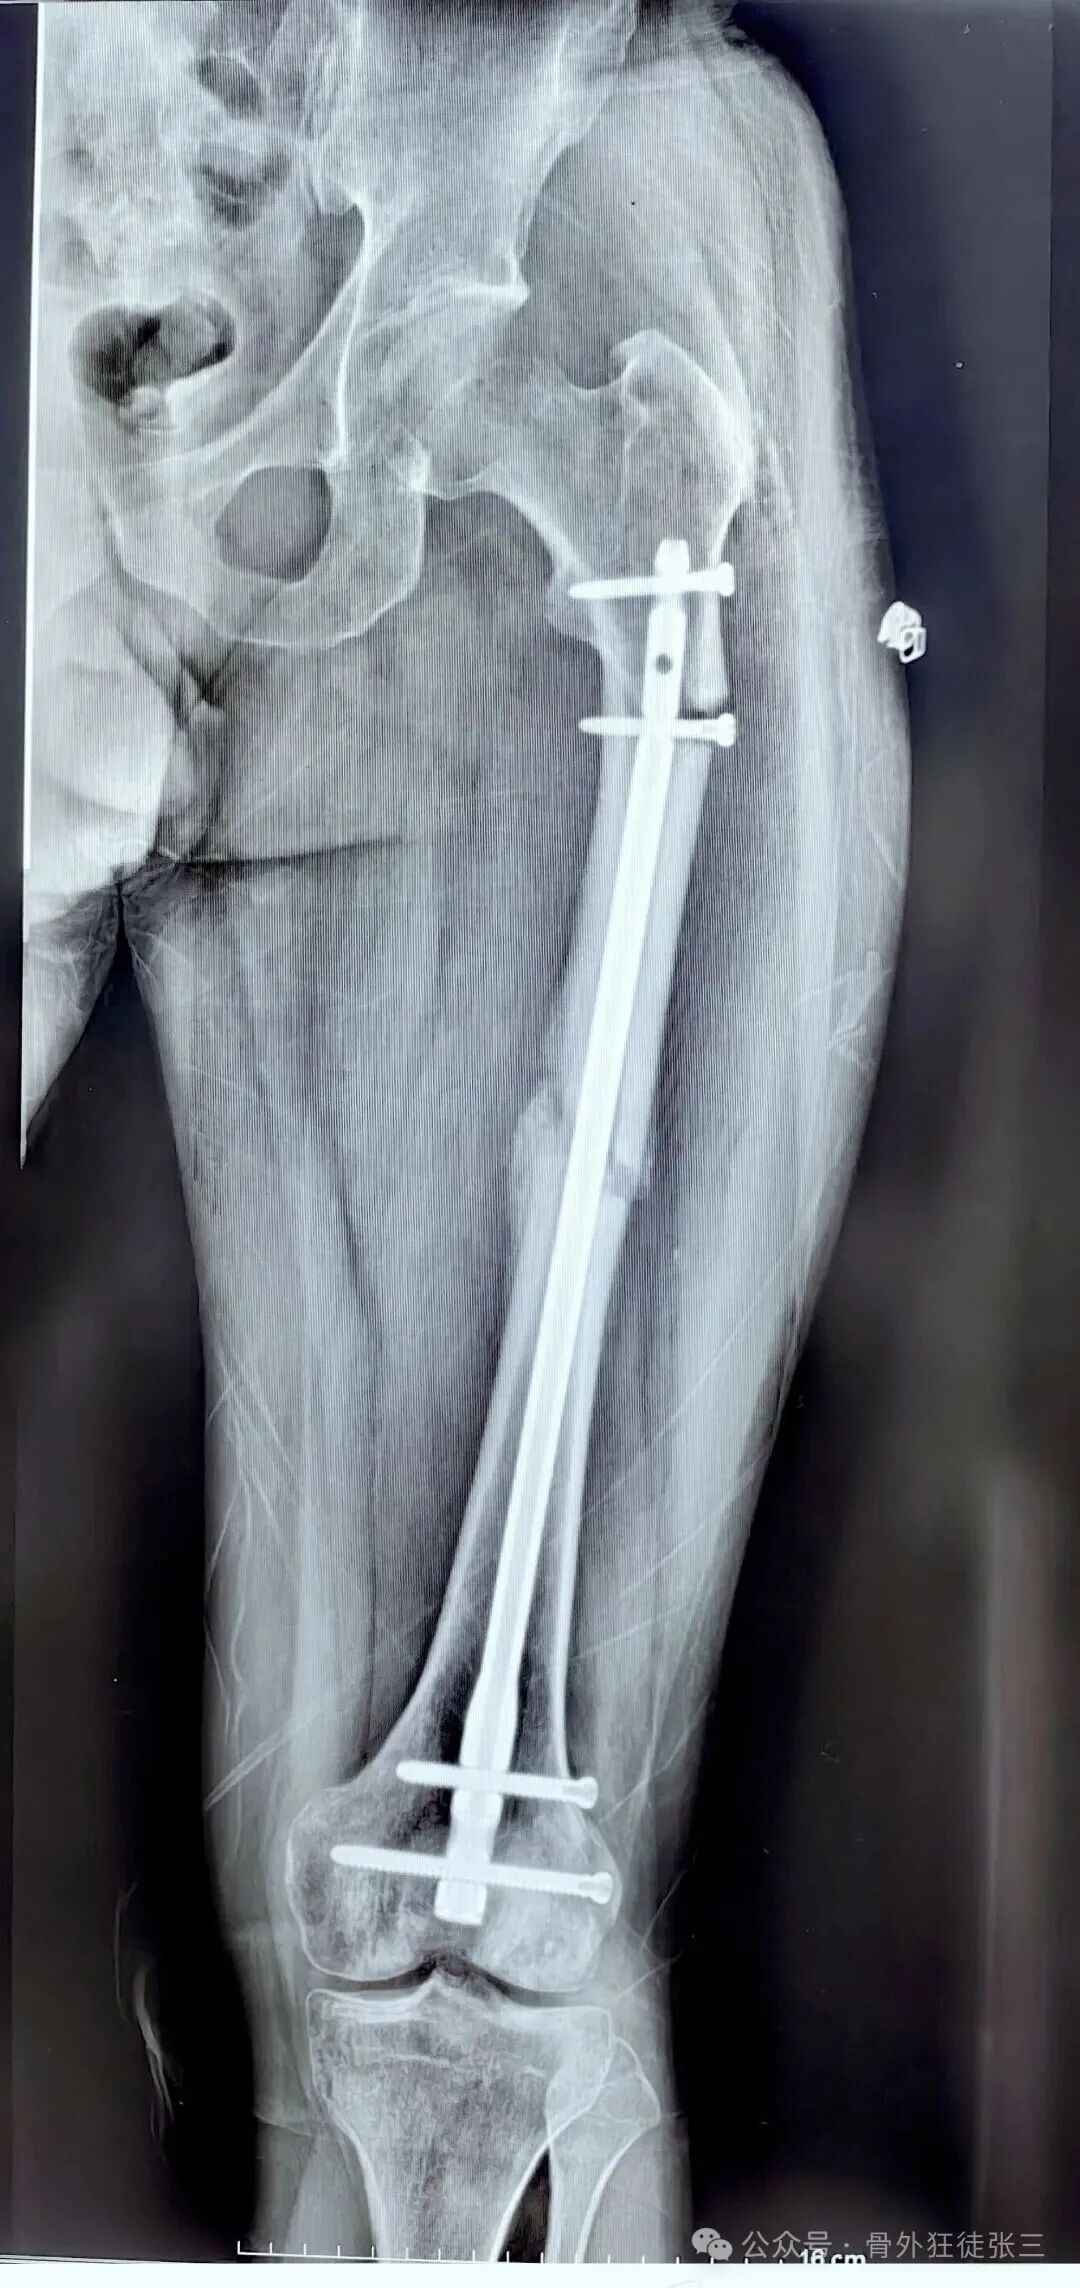

病例一:

26岁,男性,骨质非常好

初次手术主刀选择了

1,逆行髓内钉

2,切开复位

单从片子上看

手术做的也挺好

复位也好

钉子长度也好

我们给予翻修

1,顺行髓内钉,头颈模式

2,全长保护,

3,最粗,够长

4,扩髓约等于植骨

术后5个月完全愈合